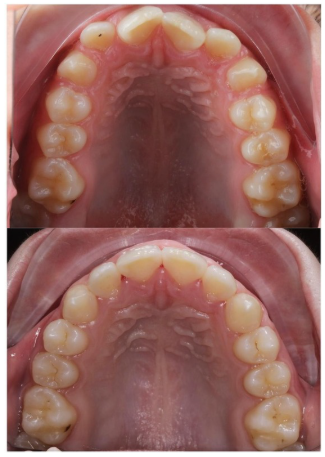

- Escaneado Digital Intraoral: Hemos sustituido las incómodas pastas de impresión por un escáner 3D. Obtenemos una réplica exacta de la boca del adolescente en segundos.

- Planificación Virtual: Diseñamos el camino hacia la sonrisa perfecta antes incluso de colocar el primer bracket.